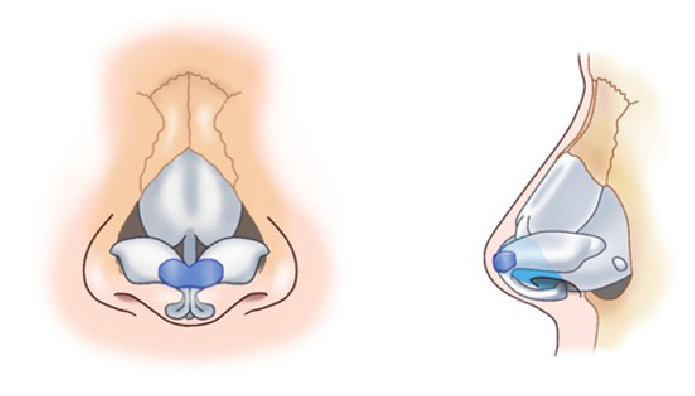

鼻中隔延長術を行った後、感染や何らかの原因で強い炎症を伴って鼻先が拘縮してしまった場合、時期を待って肋軟骨移植による修正を行う方法があります。

拘縮し鼻先や鼻尖が後退している状態の改善を図るため、open approachから拘縮をできるだけ解除します。

肋軟骨で作成したL型フレームを移植します。

肋軟骨L型フレームを外側鼻軟骨と前鼻棘に縫合固定します。

鼻翼軟骨をL型フレームに引き上げ固定します。

必要に応じて鼻柱部分に軟骨移植を追加します。

鼻先を耳介軟骨や軟部組織でカバーします。